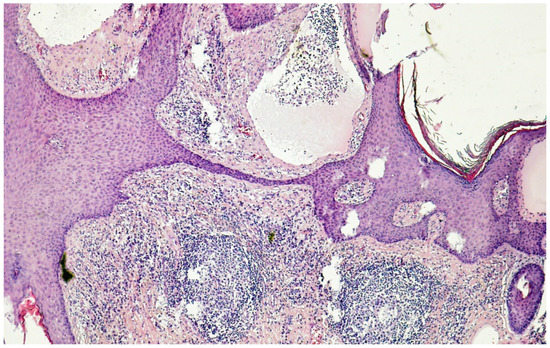

- Plaza, J.A.; Requena, L.; Kazakov, D.V.; Vega, E.; Kacerovska, D.; Reyes, G.; Michal, M.; Suster, S.; Sangueza, M. Verrucous localized lymphedema of genital areas: Clinicopathologic report of 18 cases of this rare entity. J. Am. Acad. Dermatol. 2014, 71, 320–326. [Google Scholar] [CrossRef]